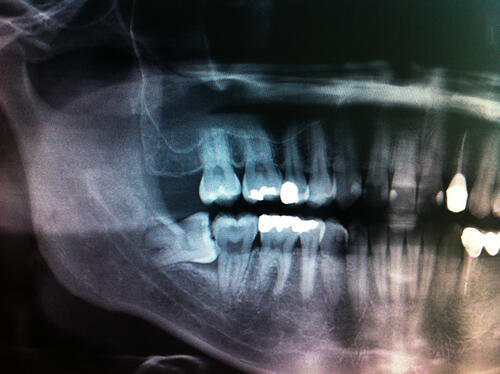

Для принятия решения врач может сделать рентгенограмму зубов мудрости.

На ее основании он приходит к выводу, есть ли достаточно места для их прорезывания, или же следует их удалить во избежание ретенции.

Рентгенограмма также помогает определить степень тяжести ретенции зуба и его расположение относительно других анатомических структур. На этом основании можно оценить сложность удаления такого зуба и составить план вмешательства, которое позволит избежать разных осложнений.